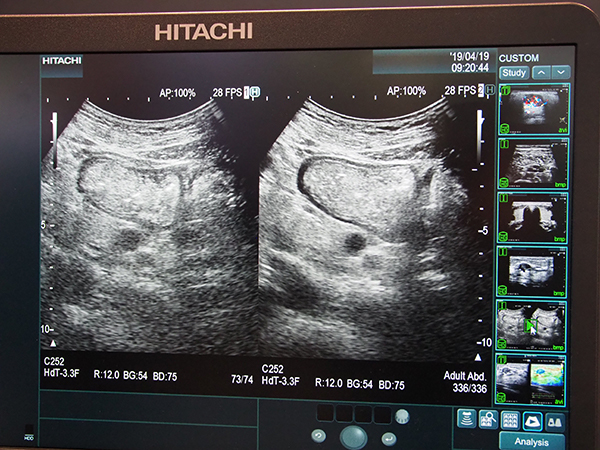

超音波診断装置は,「ARIETTA 850 / 65 / 50」を中心にアピールした。最上位機種のARIETTA 850では,新機能として“Carving Imaging”を紹介。組織の辺縁などをくっきりと見せる画像処理により,視認性の高い画像を表示する。高空間分解能を得られる“eFocusing”と組み合わせて使用することで,超音波検査の質の向上と効率化に貢献する。

新機能“Carving Imaging”(右)では視認性が向上